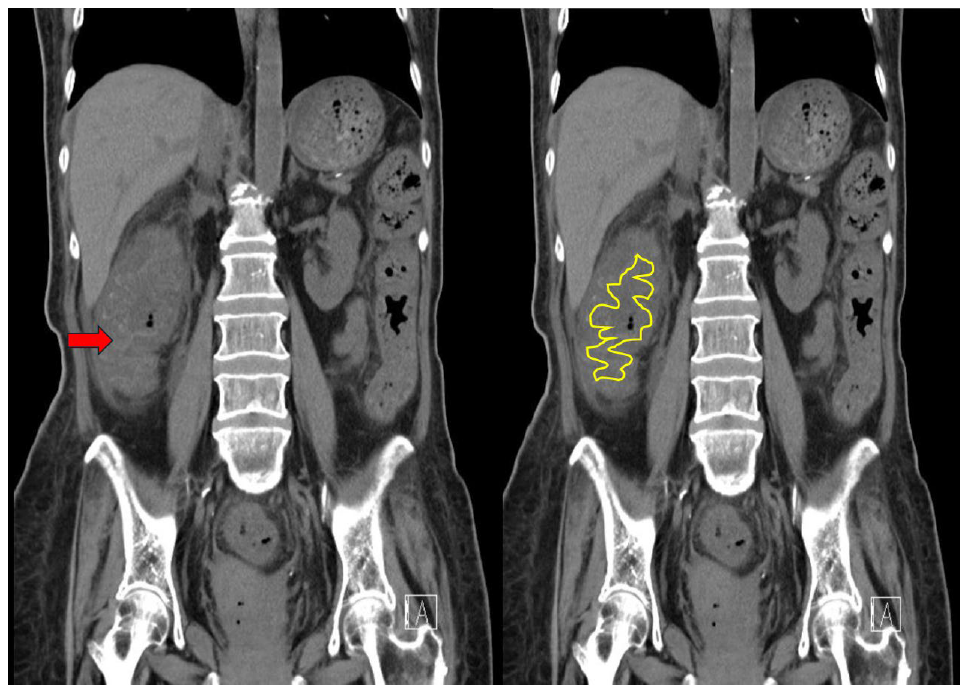

圖三腹部電腦斷層(未施打靜脈顯影劑) (縱切)。升結腸腸壁腫脹嚴重,腸道空腔腫漲至很小甚至幾乎看不到腸腔(lumen)。升結腸內可見亮度比較高的黏膜,主要是因為黏膜充血發炎(紅色箭頭)。黃色線條描繪,明顯腫脹的大腸結腸帶皺摺 (Haustra fold),稱為thumbprinting。

本個案,圖三的未施打靜脈注射顯影劑的腹部電腦斷層影像中,黃色線條包圍的出現“亮的”高顯像呈現,此時呈現的pattern,稱之為accordion sign (concertina sign),主要以比喻和手風琴(Accordion)的皺褶結構相似(如圖四),accordion sign的CT影像,腸道壁變厚,腸壁mucosa充血變厚後呈現“亮度高”CT顯像,延伸至mucosa與submucosa腫脹的組織間。主要的成因可為“口服顯影劑”進入腫脹的大腸結腸袋皺摺和偽膜(pseudomembrane)之間,或因“發炎反應誘發細小的新血管生成”充斥於腫脹的腸壁。這個accordion sign,主要為嚴重的偽膜性腸炎(pseudomembrane colitis)的特異性影像表現,在其他研究文獻,指出此影像表現亦可可於感染性和缺血性腸道疾病。

1. 此個案在病史方面,腹瀉一週的情況,CT上出現的表徵有:target sign, accordion sign, thumbprinting,侵犯的範圍主要是大腸(全段大腸),腸壁呈現明顯腫脹(大部分> 1公分),腫脹表現呈現不規則環狀離心的腫脹,懷疑是偽膜性結腸炎。佐以臨床檢測個案糞便的Clostridium difficile toxigenic gene detection呈現陽性,繼而確定診斷。